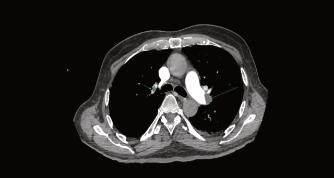

EnCDIcontamosconlatecnologíaparalarea‐lizacióndeestudiosdiagnósticos,asegurando unacorrectaevaluacióndelospacientes.(Fig 3y4).Estopermitirálaidentificaciónprecoz depotencialescomplicacionespulmonares post-COVID-19,conelfindequeelmédico tratanteproporcioneeltratamientoadecuado yevitarsecuelasposteriores.